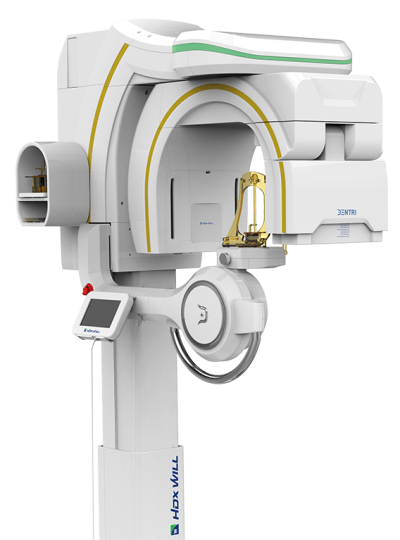

Introducing the Dentri Max, a game-changer in dental imaging tailored just for you! With its impressive Field of View (FOV) of 18 x 16.5cm, this model promises visually stunning images that redefine precision diagnostics.

Designed to cover a wide spectrum of dental needs, the Dentri Max is your all-in-one solution for endodontics, implantology, craniomaxillofacial, and cephalometric analysis. Say goodbye to blurry images and hello to crystal-clear clarity, thanks to its cutting-edge image-processing algorithm and metal artifact reduction technology.

But that’s not all – the Dentri Max goes above and beyond with features like extraoral bite-wings, FMX from panoramic shots, 3D picture superimposition, and one-step airway analysis. It’s like having a complete 2D/3D imaging package right at your fingertips, tailor-made for every aspect of your practice.